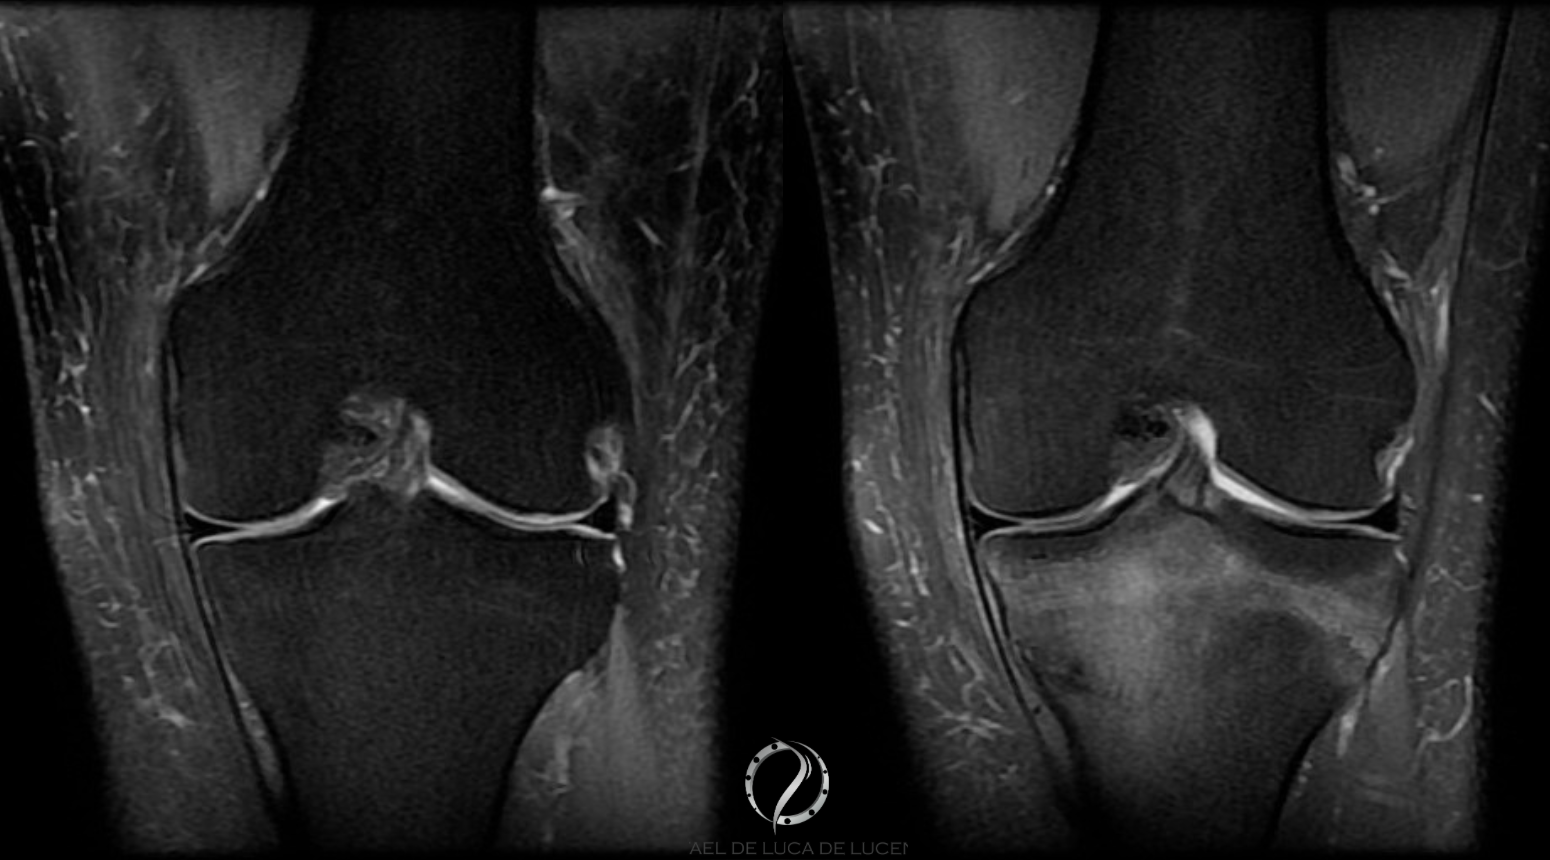

- Ressonância Magnética (RM): padrão-ouro para diagnóstico, detectando edema ósseo, microfraturas e graduação da lesão.

A classificação do risco é essencial:

- Baixo risco: fraturas em áreas de boa cicatrização (tíbia posteromedial, fêmur medial).

- Alto risco: fraturas na cortical anterior da tíbia ou patela, com maior chance de não união.